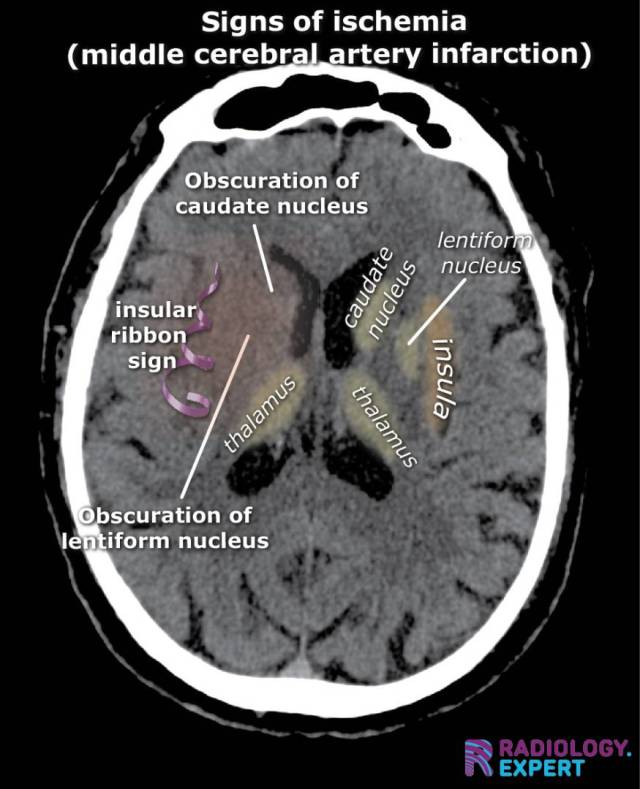

ischemic sigs MCA infarction on CT. Insular ribbon sign. Blurring basal ganglia ischemic sigs MCA infarction on CT. Insular ribbon sign. Blurring basal ganglia

Click image to see overlay